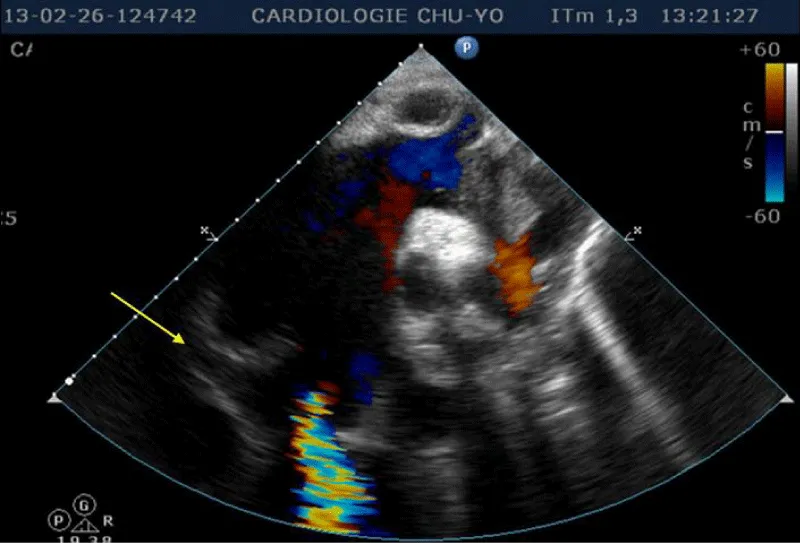

Transthoracic echocardiography (Figures 3,4) found a dilated aortic root (52 mm) with an ultrasound image of the intimal flap, and significant bi-ventricular dilation (left ventricular end-diastolic diameter of 72 mm). Systolic functions of both ventricles were severely impaired (LVEF of 24% and TAPSE of 10 mm). There was severe aortic regurgitation with a regurgitant orifice area of 35 mm². Dissection of an aortic aneurysm on dilated cardiomyopathy was diagnosed and confirmed by aortic CT scan (Figure 5); it was a type A aortic dissection with very severe dilation of the aortic root at the origin of the first branch of the supra-aortic trunks. A Type B dissection coexisted along, with an aortic dilation beginning far from the origin of the last branch of the supra-aortic trunks up to the iliac bifurcation. The Marfan disease was diagnosed despite the absence of genetic testing and a family history of the syndrome. An ophthalmological assessment could not be carried out. Medical treatment with diuretics, vasopressin amines, and analgesics was started and enabled slight improvement. The patient was later referred for surgical management through the financial support of a philanthropic sponsor. He was operated on March 7th, 2013 under cardiopulmonary bypass, using the Tirone David procedure. During surgery, the impression of two separate aortic dissections was confirmed: the former one of type B which previously went unnoticed, and the recent one of type A which determined the patient current clinical condition. After surgery, congestive heart failure was persistent, but during follow-up in the outpatient unit, the clinical condition remained stable under diuretic, ACE inhibitor, and oral anticoagulation. Unfortunately, the patient died four years later in 2017, due to poor medical follow-up.

Figure 3: Transthoracic heart ultrasound suprasternal incidence: note the aneurysmal dilatation of the ascending aorta, aortic leakage, presence of an intimal tear and intimal flap (arrow).